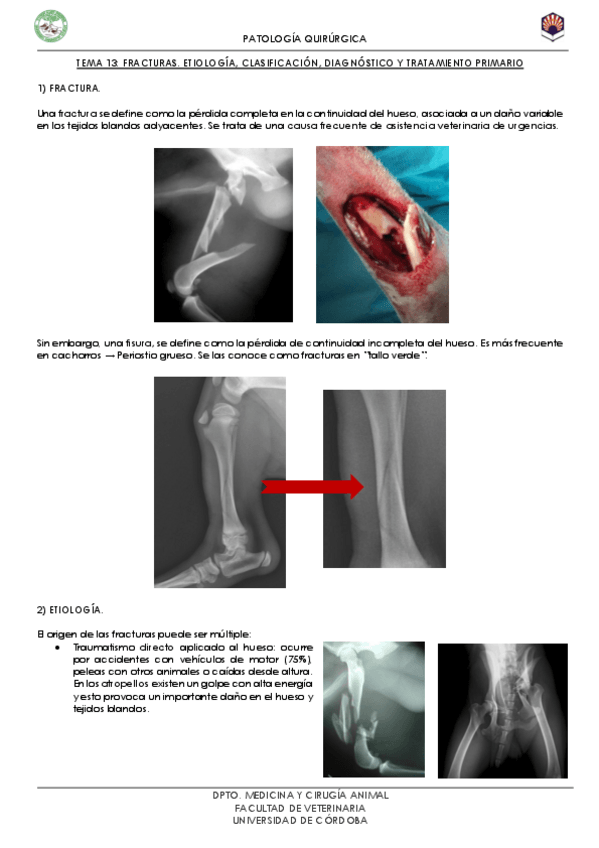

TEMA-13-FRACTURAS.pdf